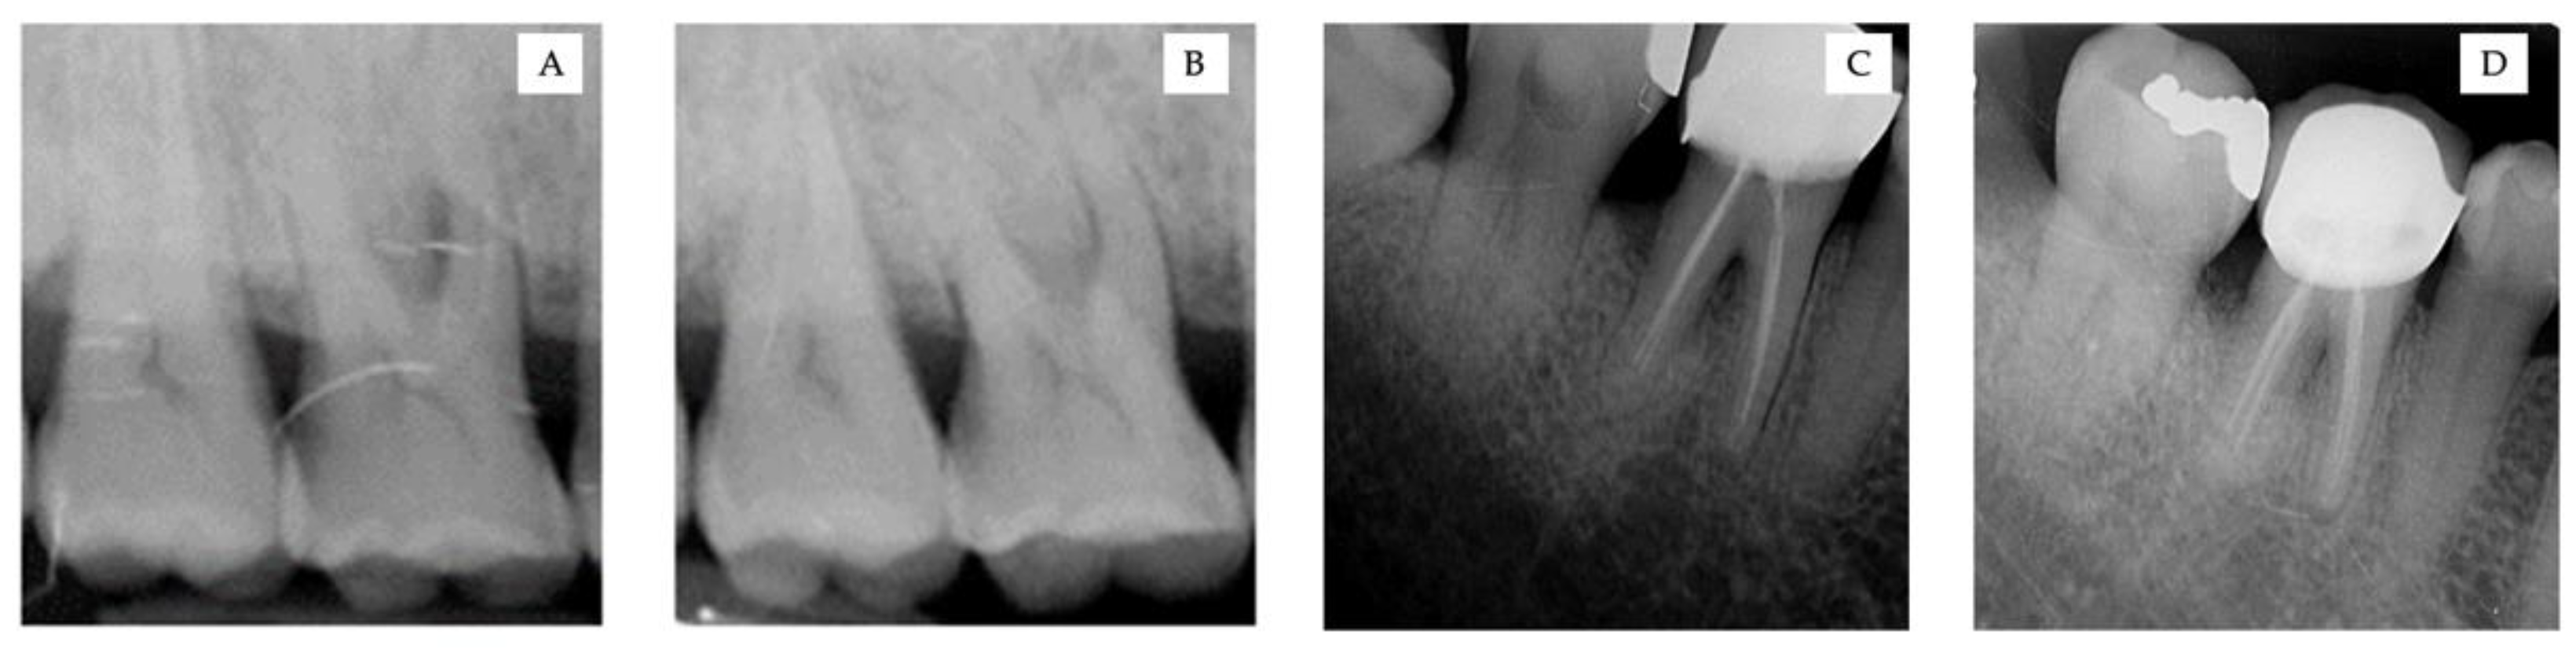

2.3. Surgical Procedure

3.2. Clinical and Radiographic Measurements